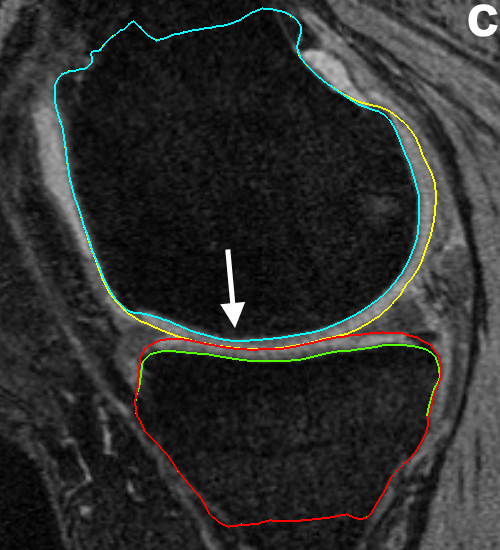

Fig. 7 qualitatively compares the segmentation accuracies between the gradient-based costs and the hierarchical classifier with respect to the independent standard. Both the femur and tibia are shown with their respective bone and cartilage segmentations showing good agreement between learning-based segmentation and the independent standard.

Fig. 8 qualitatively shows the improvement of 4D LOGISMOS over 3D. Note the lack of an obvious edge distinguishing the tibia and femur cartilage. Using the spatial and temporal contextual information from all the time-points, the 4D method is able to correctly position the cartilage for the tibia and femur despite the lack of image information locally.